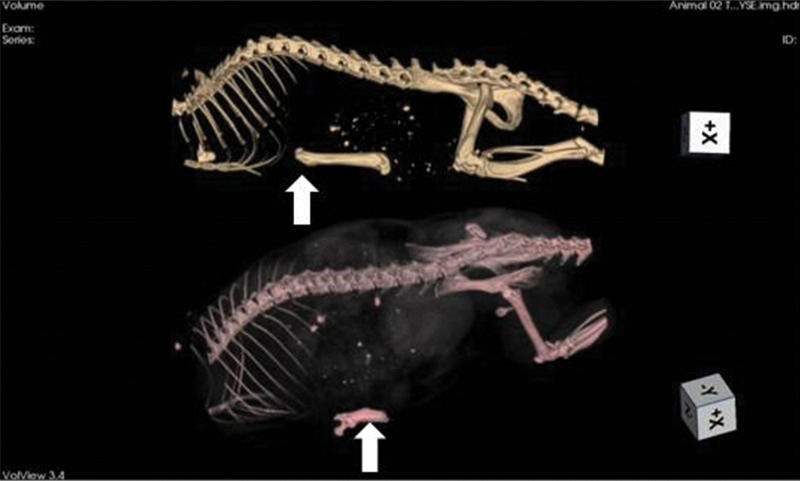

Shortly after femur grafting (baseline), tomographic imaging was performed (Figure 2).

Tomographic imaging of an animal immediately after syngeneic femur implant (upper image) and at 60 days of storage (lower image). The grafts (arrows) can be identified below the rib cage. On the 60-day image, the bone resorption is highly advanced (nearly 50% of the mass). This phenomenon did not always occur, with other animals exhibiting far less bone loss.

After 30 and 60 days, the inflammatory tissue reaction around the bone continued to occur, although less hyperemia was observed. Bone edema disappeared and was replaced by progressive brittleness and resorption. By 60 days, bone resorption and fragmentation were conspicuous, and in certain animals, as little as 50% of the original femur could be recovered from the subcutaneous pouch. Bone marrow changes suggestive of necrosis were also noted at 30 days and were more remarkable after 60 days (Figures 2 and 4).